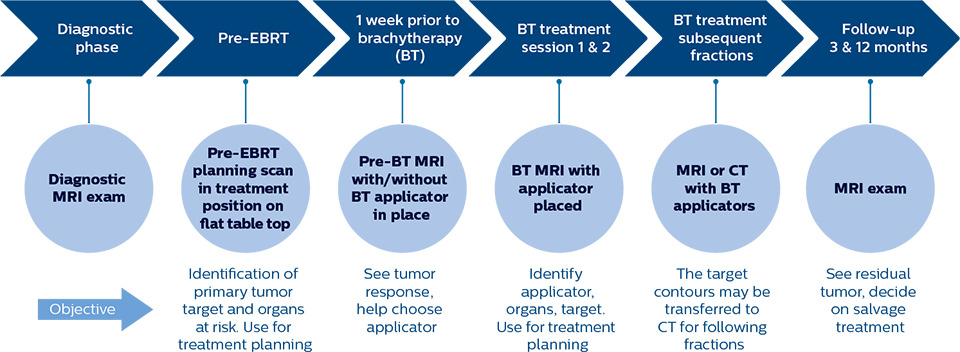

MRI is important at all stages of cervical cancer radiotherapy

At AUH, MRI plays a role across the entire patient trajectory for cervical cancer radiation therapy patients. “Our workflow is closely based upon the GEC-ESTRO guidelines,” says Dr. Tanderup.

“In patients referred for cervical cancer treatment at our hospital, MRI has already been part of the diagnostic process. Before initiation of EBRT, PET-CT and MR treatment planning scans are acquired with the patient in treatment position on flat table top.

The images are fused and used for MRI-guided target definition of the primary tumor and for PET-guided definition of pathological lymph nodes.

Then we perform pre-brachytherapy MRI within one week before the first brachytherapy session. This MRI exam is done with a dummy applicator in place to establish the geometry we are going to see at brachytherapy. This MRI exam allows us to see how the tumor responded to EBRT and we also use it to decide which kind of applicator the patient needs. For instance, if we see a very advanced tumor with poor regression, we need a more advanced applicator which combines intracavitary and interstitial brachytherapy.”

At Aarhus, MRI plays a role across the entire patient trajectory for cervical cancer radiation therapy